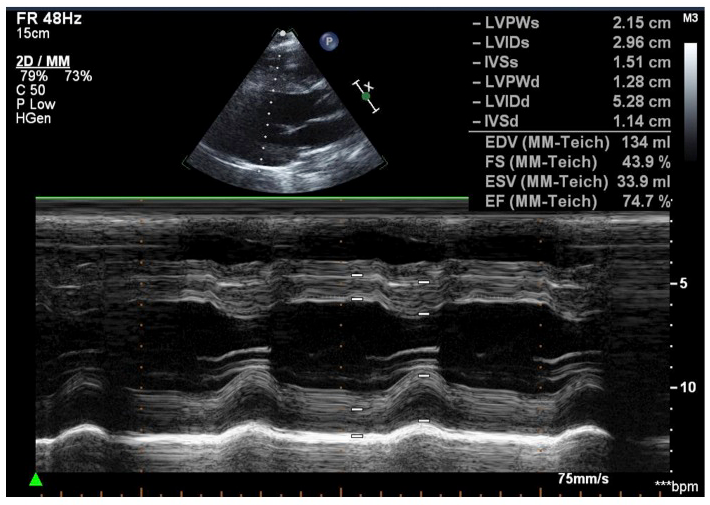

A transthoracic echocardiogram was ordered was within normal limits. Reported values are show in Figure 3 and M-mode measurements are shown in Figure 4.

FIGURE 4